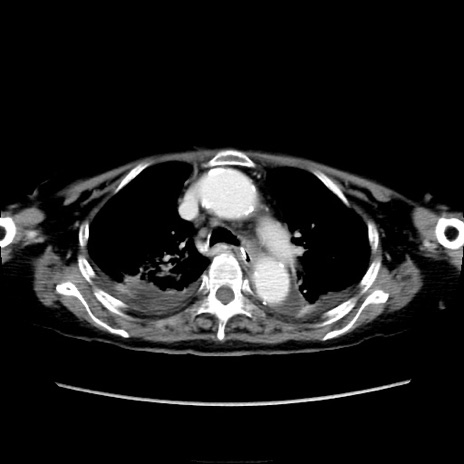

冠状断像

他院CT